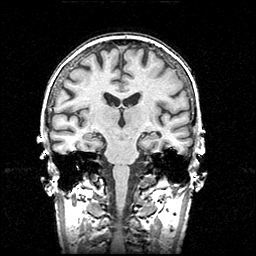

MR Study #1 -- Slice #61

[Home][Help][Clinical] Slice 61